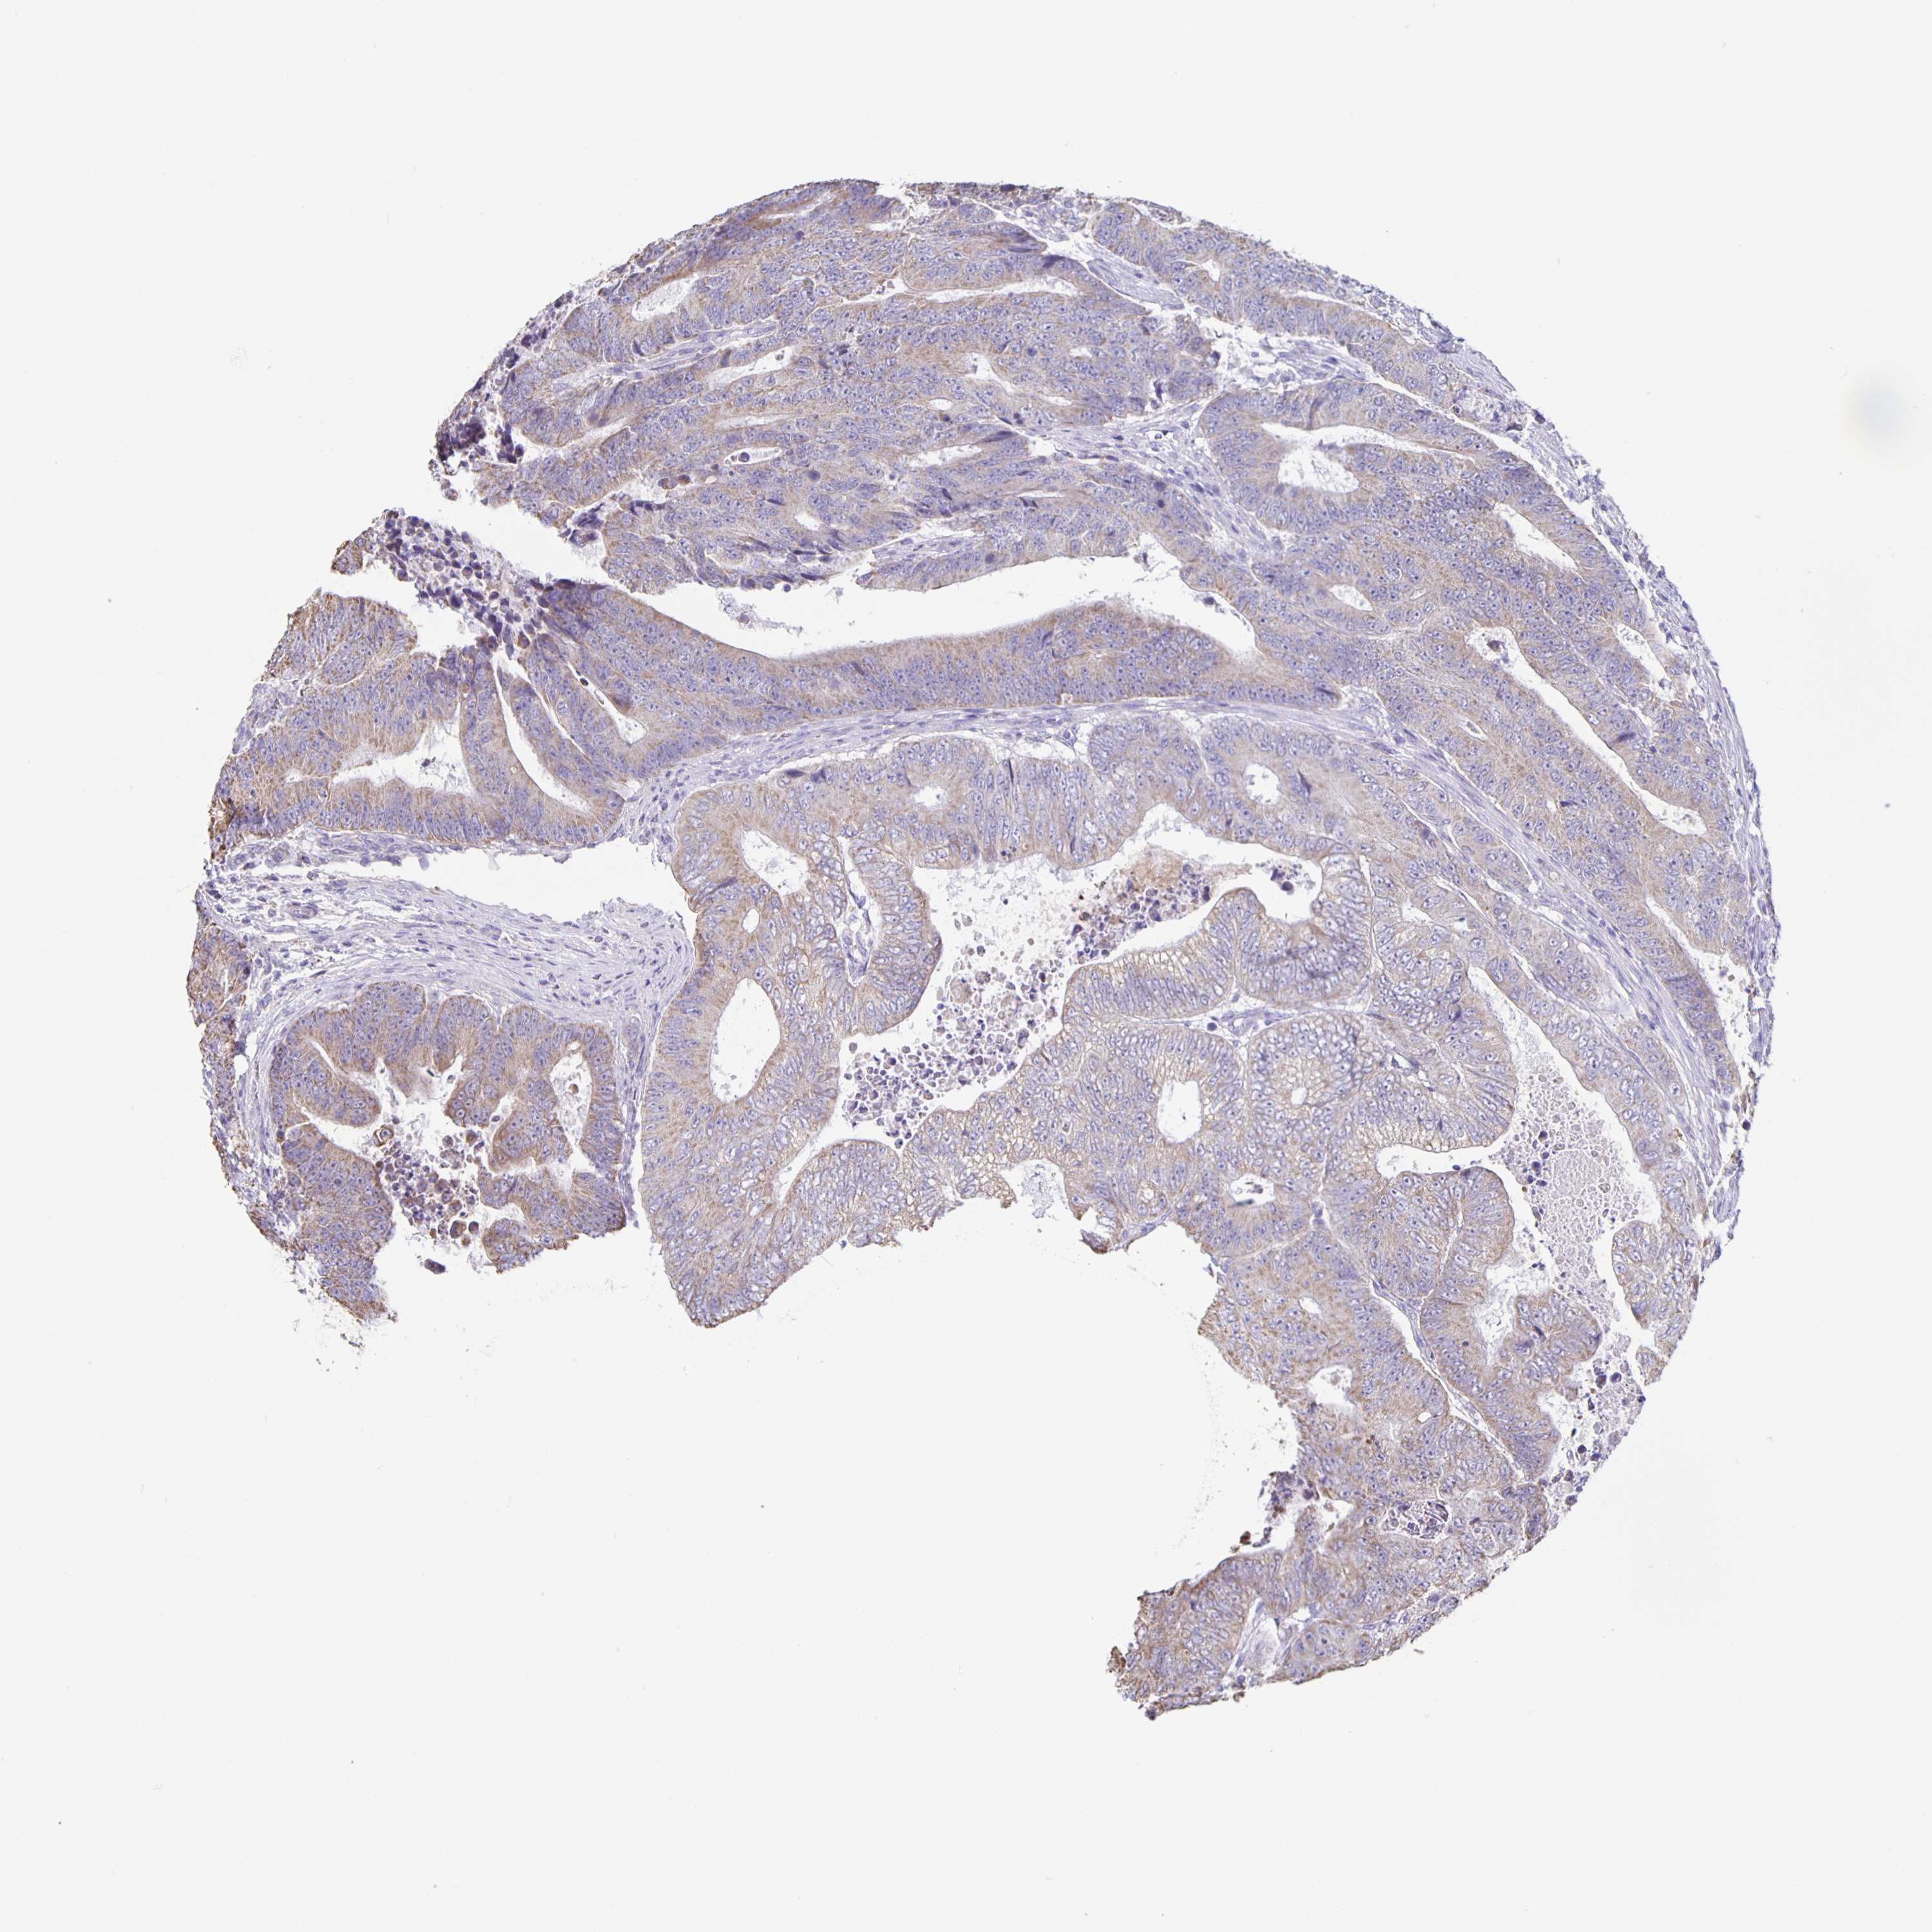

CANCER COLORECTAL CANCER Show tissue menu

Colorectal cancer

Human cancer

Colon adenocarcinoma